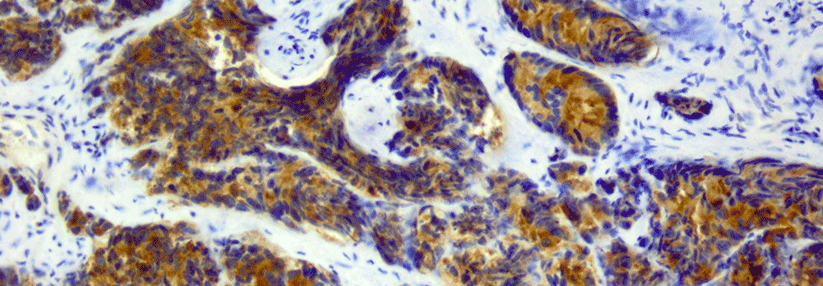

Etwa drei Viertel der Patienten aus der Hochrisikogruppe wurden biopsiert. In 43 Fällen wurde ein Karzinom diagnostiziert. Das entspreche einer Prävalenz von 0,19 % auf fünf Jahre. Ein weiteres wichtiges Ergebnis sei, dass entgegen publizierter Daten die Mehrzahl dieser Karzinome nach den ISUP*-Kriterien als harmlos eingestuft wurden. Nur vier Tumoren waren unmittelbar behandlungsbedürftig.